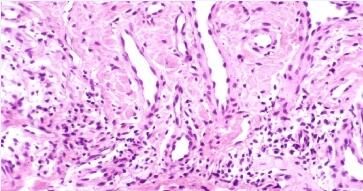

日光性荨麻疹发病机制尚未明确,通常为特发性。日光性荨麻疹患者对致病光谱的敏感性和光谱范围也可发生改变。

北京京城皮肤医院认为日光性荨麻疹发病机制为:患者血循环中存在某种色基,循环至皮肤并在日光照射情况下转变成光变应原(photo allcrgetl)而致病。少数继发于5LE、红*生成性原卟啉病,偶可作为化学物质(如沥青)和某些药物的光敏性反应。光敏试验(单色或广谱光源)阳性可证实诊断和确定致病光谱。